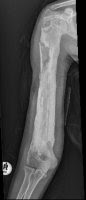

The same child as above at about 1 month after presentation. A periosteal reaction can be seen and the femur is osteopaenic. The osteomyelitis has not resolved despite drainage and antibiotics and is becoming chronic. At this stage there is a real danger of femur fracture

X Ray of right femur of the above child 1 year later. Chronic osteomyelitis has developed and the femoral shaft has become sclerotic with invulucrum (new bone) formation. A sequestrum can be seen in the upper third of the shaft.

Lateral x ray.Note the sequestrum appearing as a 'bone - within - a - bone'